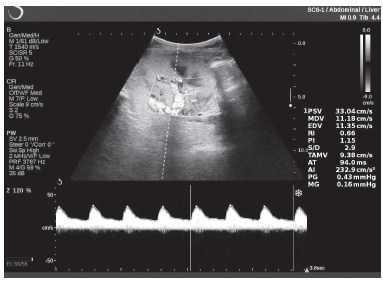

Клинический пример из первой группы. Пациент М., с хронической почечной недостаточностью. Трансплантация почки произведена от живого родственного донора. Трансплантат находится в правой подвздошной области. При нормальном функциональном состоянии трансплантата, показатели цветовой и спектральной допплерографии оценивались как удовлетворительные, с индексом резистентности не более 0,60 (рис. 1); показатели жесткости паренхимы почечного трансплантата при УЭСВ на различных участках составили от 20,05 до 29,18 кПа (рис. 2-4).

Рисунок 1. Ультразвуковое исследование в режиме цветовой и спектральной допплерографии в междольковых и сегментарных артериях у пациента М. Показатели кровотока в данном случае не изменены